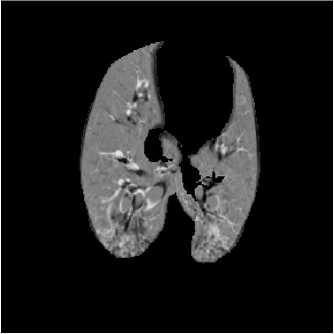

For each animal, approximately 200 automatically identified landmarks within the lungs are used to compute registration accuracy. The landmarks are widely distributed throughout the lung regions. Figure 5 shows an example of the distribution of the landmarks in animal D for both the and images. The coordinate of each landmark location is recorded for each image data set before and after registration for all four animals. Figure 6 shows the landmark distance before and after registration for four animals. The grey boxes show the magnitude of respiratory motion during the tidal breathing. For all four animals, before registration, the average landmark distance is 6.6 mm with a minimum distance of 1.0 mm, maximum distance of 14.6 mm, and standard deviation of 2.42 mm. After registration, the average landmark distance is 0.4 mm with a minimum distance of 0.1 mm, a maximum distance of 1.6 mm, and a standard deviation 0.29 mm. The trends for all animals are consistent and the results demonstrate that the registrations produced good anatomic correspondences. All registrations were examined and it was confirmed that all Jacobian values had positive values.

Figure 5(a) shows the location of the (Xe-CT) slab overlaid on the image. Figure 7 shows an example of the image registration result from the image to the image. The first row shows the misalignment between the images before image registration. Though the images were acquired without moving the animal between the scans, there is still non-rigid deformation between scans as shown in Fig 7(d), as the black and white regions represent the large intensity difference between Fig. 7(a) and (b). In addition, the slice thicknesses were quite different which causes partial volume artifacts. After image registration, the image is aligned to the image, and the resulting difference image (shown in Fig. 7(e)) is near zero. The transformation from the to the image allows us to map the Xe-CT sV into the coordinate system of image. Note that since the regions outside the lung are not included in the registration process, the mediastinum and other body tissues are not aligned. Also note that the dorsal region of the lung shows a intensity difference after registration. This is due mainly to the gradual progression of atelectasis and tissue edema during the course of the experiment.